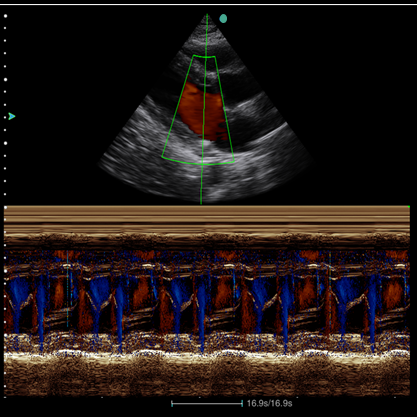

⦁ TDI

⦁ VS Flow

⦁ Strain Rate

Tecnologias avançadas

A tela destacável e os softwares de cardiologia compõe com exatidão algumas das tecnologias avançadas que o C7 Plus é capaz de proporcionar ao seu usuário.